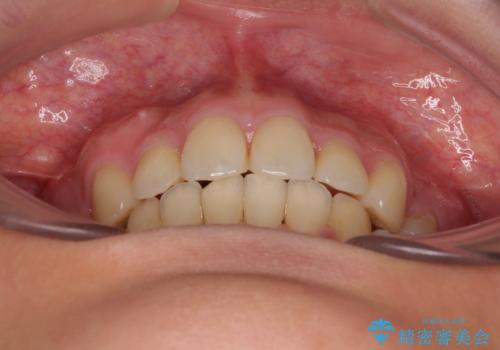

全顎的なデコボコと口元の突出感 ワイヤー装置での抜歯矯正で整った口元に

- 奥歯も含めて全体的なデコボコと前歯の突出感を気にして来院された患者様です。

上下左右第一小臼歯4本を抜歯し、ワイヤー装置にて矯正治療を行うこととしました。

想像以上に咬合力が強く、抜歯したスペースを閉じきるまでに長期間を要することとなりました。

前歯の突出感がなくなり、仕上がりには大変満足していただけました。